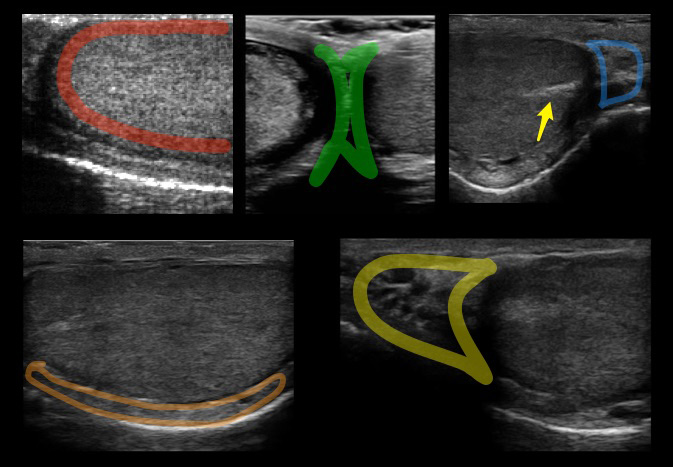

- The normal testis has midgray or medium-level echoes and is homogeneous in appearance. (Figure 3)

Figure 3. Red: Image of the normal testicle with homogenous echotexture. Green: Median raphe. Blue: Tail of the epididymis. Orange: Body of the epididymis. Yellow: Head of the epididymis. Arrow: Mediastinum testis seen as a linear echogenic band

- The epididymis has similar or slightly increased echogenicity as compared to the normal testis.

- The mediastinum testis is seen as a linear echogenic band running parallel to the epididymis, best seen on sagittal view.